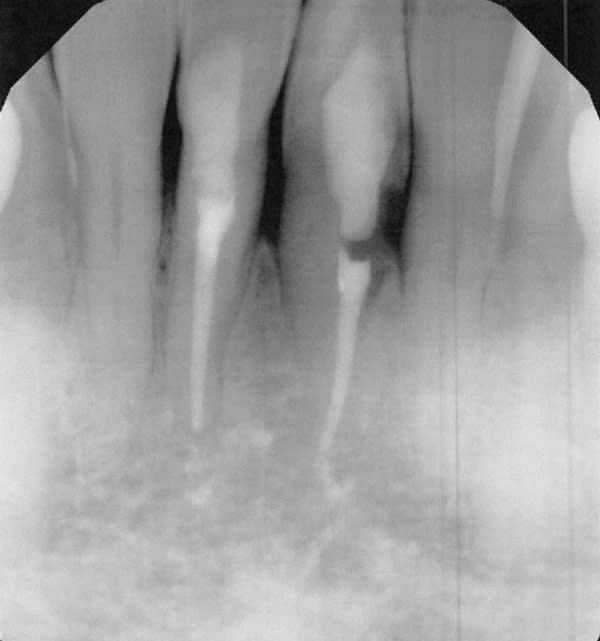

Black triangles in cervical embrasure areas are unesthetic and often cause patients to have difficulty with phonetics and hygiene. A 66-year-old woman presented to the periodontal office of Dr. Jason Stoner with excessive bleeding in the mandibular anterior region. She had a history of trauma to teeth Nos. 24 and 25 years prior, which were endodontically treated at the time of injury. Dr. Stoner's evaluation revealed a large resorptive defect on the distal extent of tooth No. 24. After considering different treatment options, the patient opted for removal of No. 24 and orthodontic therapy to achieve space closure post-extraction. Prior to removal of the tooth, Drs. James Hutta and Jeff Price were added to the treatment team to assist with orthodontics. Dr. Stoner extracted tooth No. 24 without complication, and the orthodontic phase took approximately 18 months. Upon completion of orthodontics a large residual black triangle remained between teeth Nos. 23 and 25. At this time, the patient's previous restorative dentist placed composite bonding, which the patient was not happy with. She then was referred to the author's office for evaluation of the residual Miller Class III defect. Exploiting the many benefits of bioactive Giomer Technology (Shofu, shofu.com), the author developed a treatment plan that would utilize both pink Giomer and white composite to satisfy the treatment objectives.